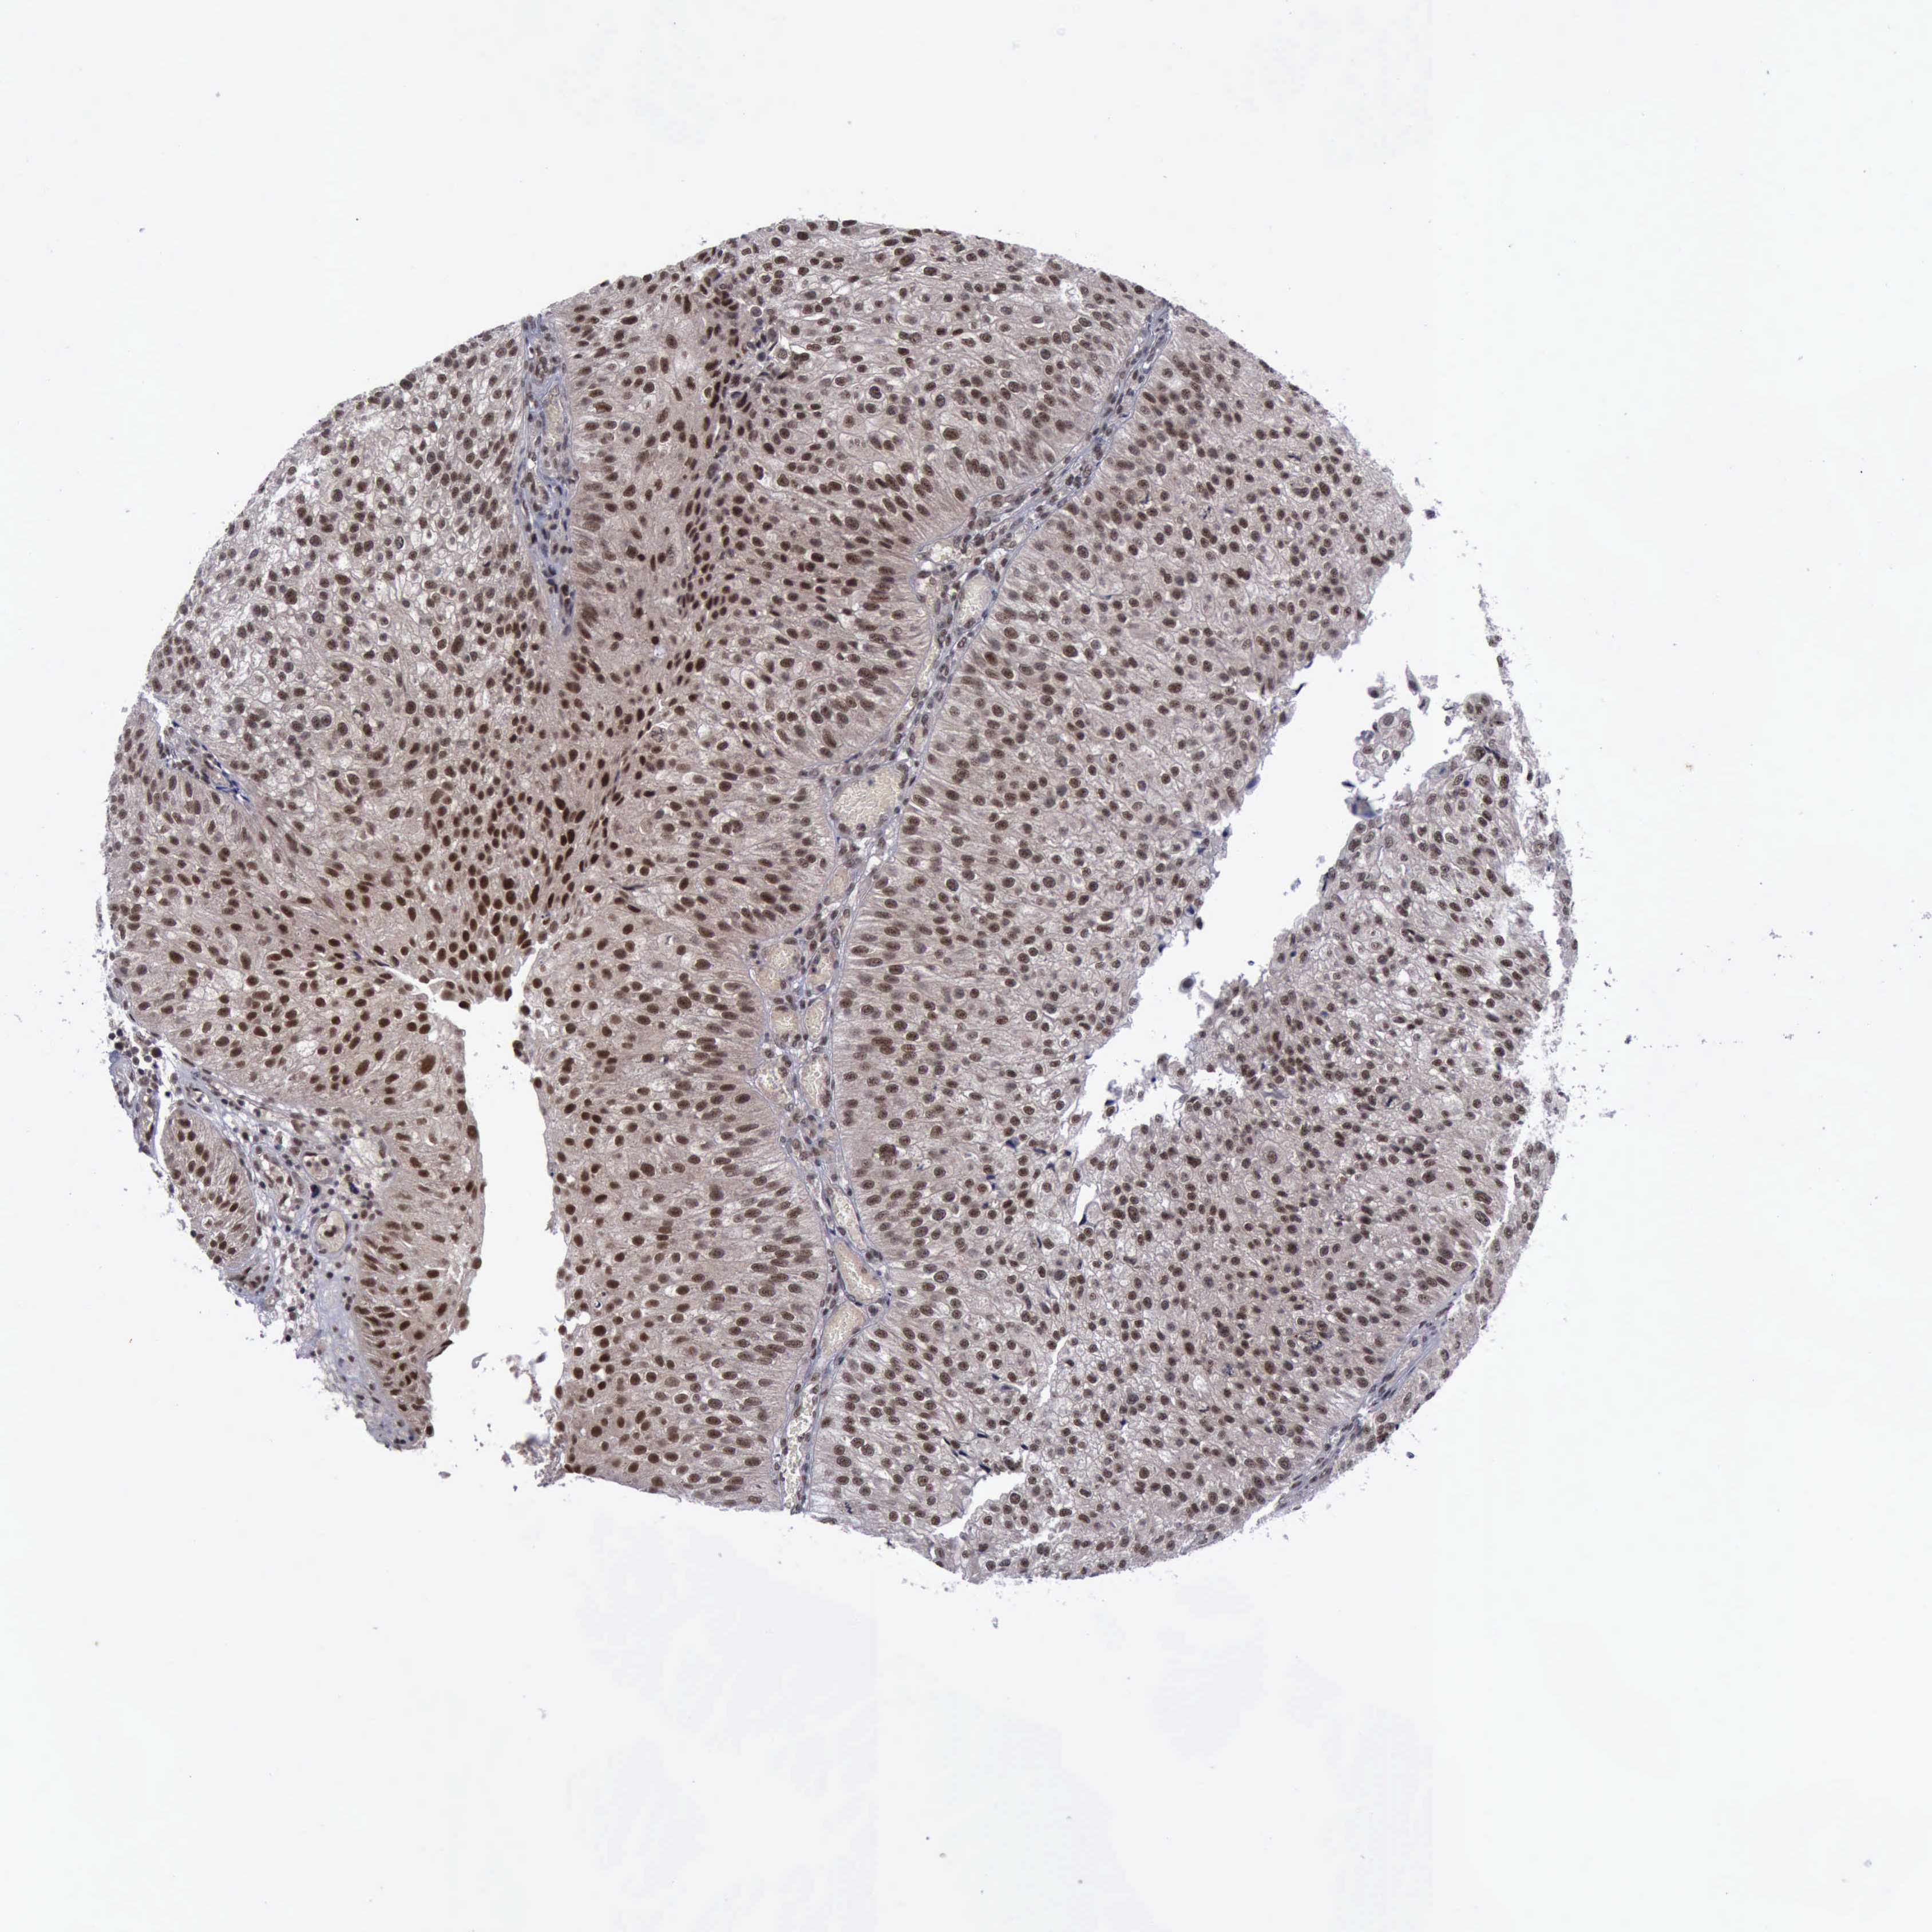

UROTHELIAL CANCER - Protein expressioni

A mouse-over function shows sample information and annotation data. Click on an image to view it in a full screen mode. Samples can be filtered based on level of antibody staining by selecting one or several of the following categories: high, medium, low and not detected. The assay and annotation is described here.

Antibody stainingi

Antibody staining in the annotated cell types in the current human tissue is reported as not detected, low, medium, or high, based on conventional immunohistochemistry profiling in selected tissues. This score is based on the combination of the staining intensity and fraction of stained cells.

Each image is clickable and will lead to virtual microscopy that enables deeper exploration of all samples and also displays staining intensity scores, fraction scores and subcellular localization as well as patient and tissue information for each sample.

Antibody CAB000102

Antibody CAB080442

Staining

High

Medium

Low

Not detected

Intensity

Strong

Moderate

Weak

Negative

Quantity

>75%

75%-25%

<25%

None

Location

Nuclear

Cytoplasmic/membranous

Cytoplasmic/membranous,nuclear

Urothelial carcinoma, High grade